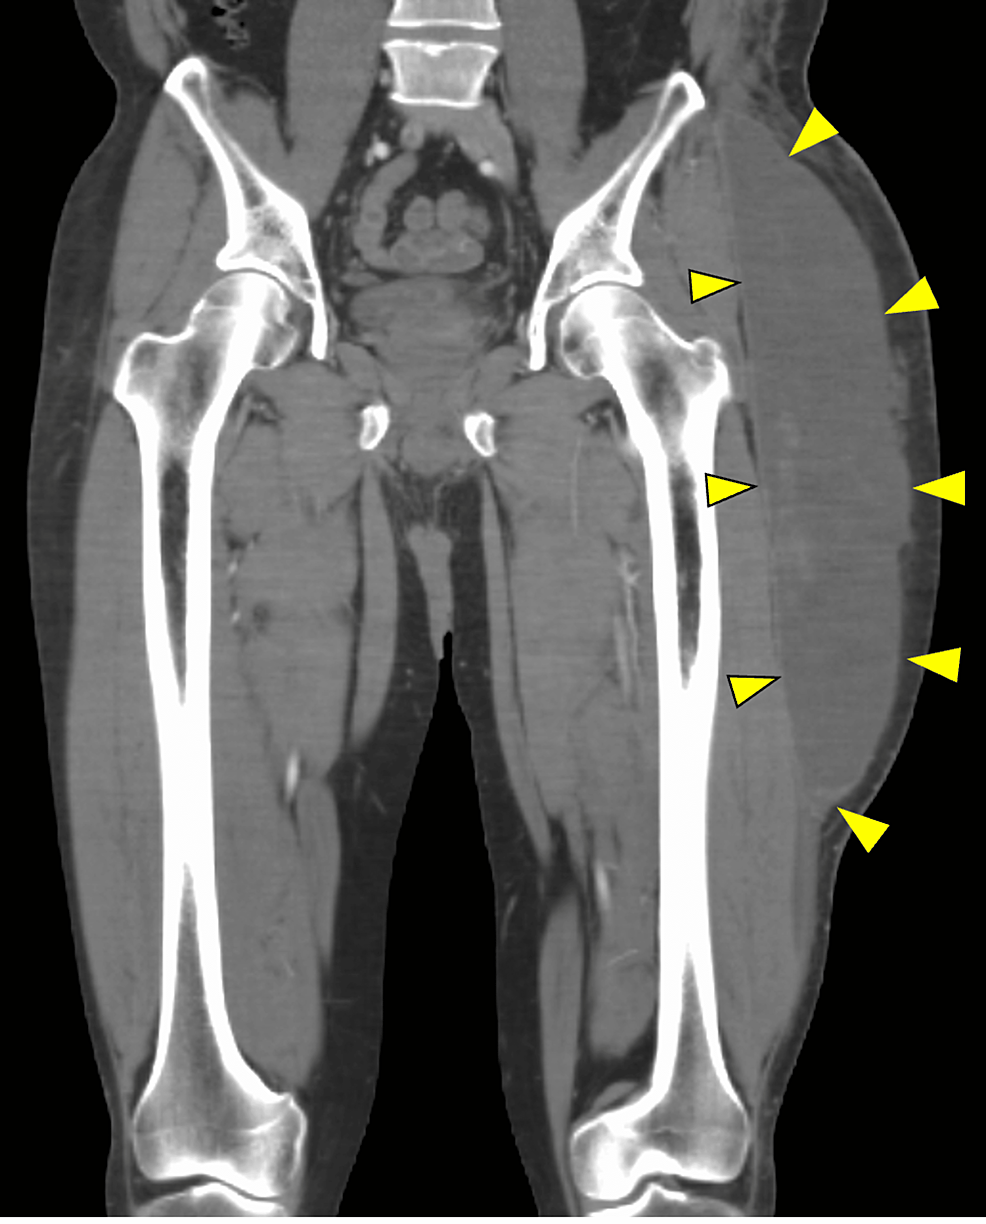

Morel Lavallee Lesion Thigh Treatment For Morel Lavallee Lesion Treatment is generally operative irrigation and debridement for most lesions given the proximity to planned surgical incisions and. It was first described in 1863 by a french physician and is. This activity reviews the evaluation and management of. The management options include nonoperative treatment, percutaneous aspiration, and open debridement. Treatment of the mll is based on lesion size, location, and. Treatment For Morel Lavallee Lesion.

Figure 1 from The treatment of a MorelLavallée lesion of the thigh Treatment For Morel Lavallee Lesion Treatment of the mll is based on lesion size, location, and proximity to the site of anticipated surgical procedures. It was first described in 1863 by a french physician and is. Treatment is generally operative irrigation and debridement for most lesions given the proximity to planned surgical incisions and. The management options include nonoperative treatment, percutaneous aspiration, and open debridement.. Treatment For Morel Lavallee Lesion.

Figure 2 from The treatment of a MorelLavallée lesion of the thigh Treatment For Morel Lavallee Lesion Treatment of the mll is based on lesion size, location, and proximity to the site of anticipated surgical procedures. The management options include nonoperative treatment, percutaneous aspiration, and open debridement. This activity reviews the evaluation and management of. It was first described in 1863 by a french physician and is. Treatment is generally operative irrigation and debridement for most lesions. Treatment For Morel Lavallee Lesion.